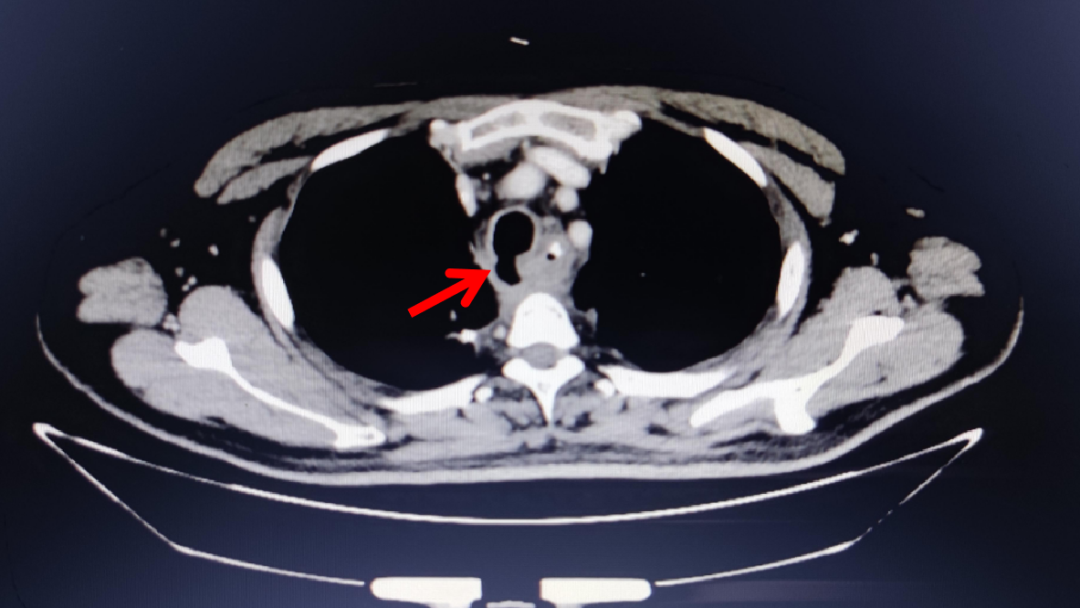

近日,我院成功为一名患者施行首例全麻下经硬质气管镜金属Y型覆膜支架置入术,巧妙解决患者气管食管瘘难题。 患者是一位56岁中年男性,诊断为食管鳞癌,患者在食管癌术后1月余开始出现进食呛咳,CT及电子气管镜检查提示:食管气管瘘(食管气管相连通,从而使食道中的食物或消化液漏入气道,引起呛咳)。 胸部CT提示食管气管瘘 针对患者病情,我院内镜中心呼吸介入治疗团队立即组织了病例讨论,在庄武主任和朱坤寿主任支持下,并请有关专家会诊,为该患者制定了科学的治疗方案——全麻下经硬质气管镜支架置入术,利用覆膜“Y”型支架覆盖瘘口,从而改善患者症状。 结合胸部CT、气管镜检查所见,根据瘘口的范围及程度,团队选取了适合的“Y”型覆膜气道支架。 在内镜中心护士长、手术室护士长、麻醉科及医院有关职能科室全力配合下,2021年10月29日中午,内镜中心呼吸内镜介入治疗团队顺利完成了本例气道支架置入术!支架置入位置精准,充分贴合瘘口,并且全程仅用时约30分钟。 患者术后恢复顺利,现已恢复进食,不再呛咳。 胸外科陈炜生博士介绍,食管气管瘘是食管癌术后的常见并发症之一,覆膜Y型金属支架置入术可有效封堵瘘口,从而改善患者症状,为手术保驾护航。